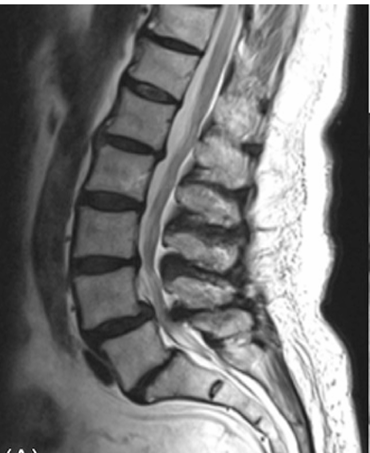

What is Decompression for Lumbar Stenosis?

A surgery to remove thickened ligaments or extra bone pressing on nerves in the lower back, creating more space for nerves.

Laminectomy or Laminotomy

Through a small incision, the surgeon removes bone or ligament pressing on nerves.